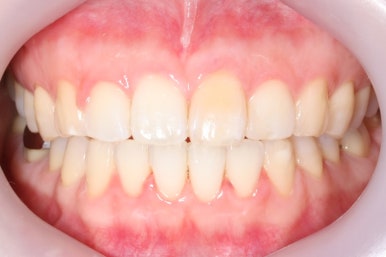

부산앞니교정 키다리아저씨치과에서 시행한 이번 MTA 부분교정의 전후 비교입니다.

위아래 앞니가 가지런해졌고, 작은 앞니의 얼룩무늬도 없어졌네요.

어쨌든, 앞니는 가지런하게 마무리가 잘 되었고, 앞니 안쪽에는 유지철사를 부착하고 치료를 종료하였습니다.